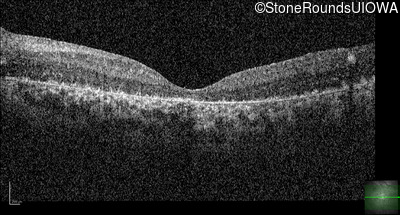

Optical Coherence Tomography - Right - 20/1000 sc

Exemplar / OCT Stack

Optical Coherence Tomography - Left - 20/500